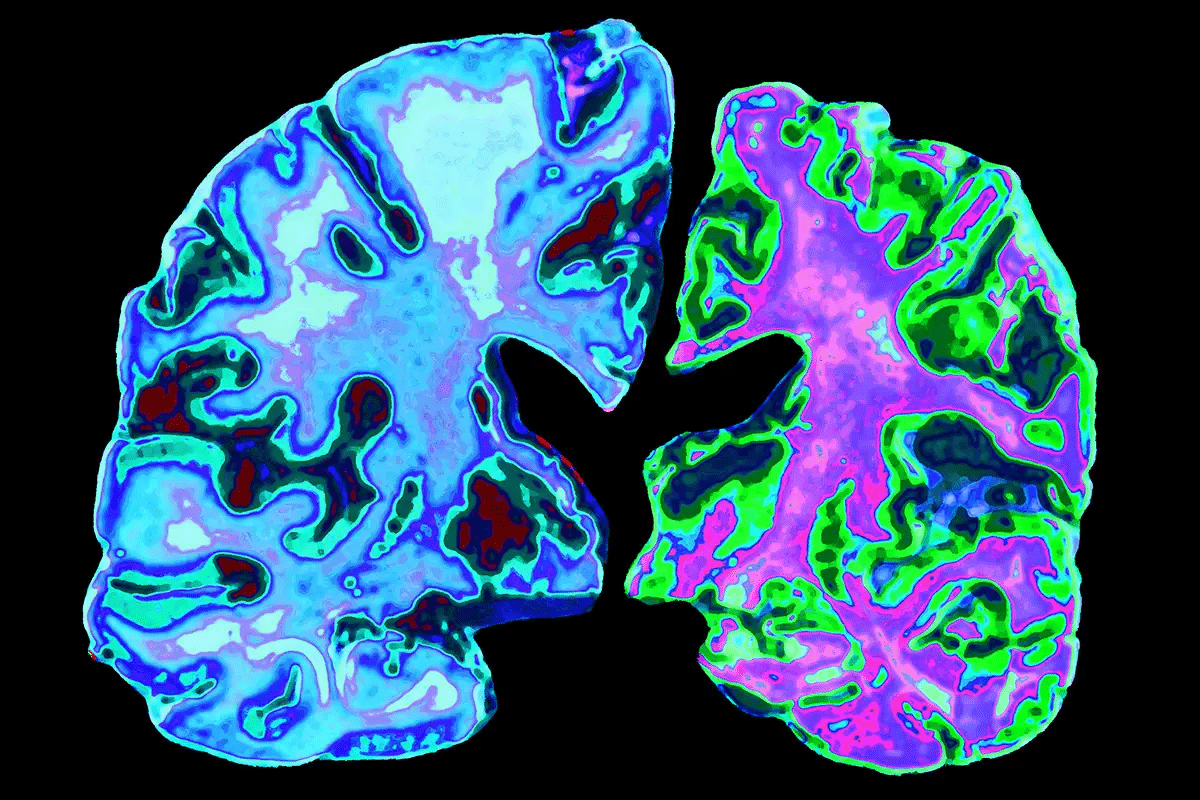

Elevated Aluminum Levels in Brain Tissue Studies

Studies have found more aluminum in Alzheimer’s patients’ brains. A key study in Environmental Health Perspectives showed higher levels in Alzheimer’s brains. Aluminum in amyloid plaques suggests it may play a role in the disease.

“The accumulation of aluminum in the brain may contribute to the pathogenesis of Alzheimer’s disease by promoting the formation of amyloid plaques and neurofibrillary tangles.”

More research backs these findings. It shows aluminum buildup in the brain may help cause Alzheimer’s.